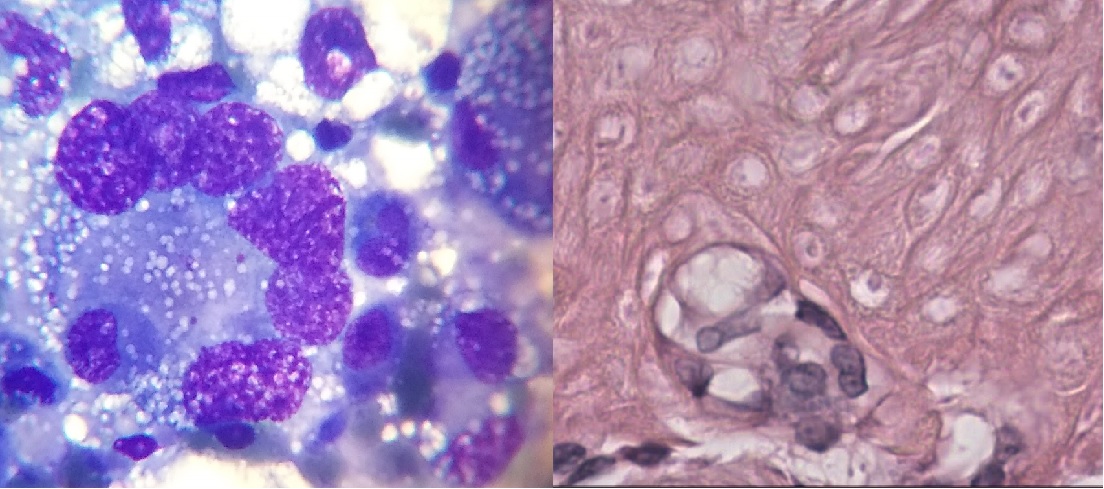

Cuando uno indica una citología lo primero a pensar es que la misma es sencilla,

económica y rápida, en comparación con la histopatología; pero cual es realmente la eficacia

diagnostica de esta herramienta. Antes de continuar es necesario comprender que la misma,

como toda técnica tiene sus limitantes y no hay que esperar más de lo que su alcance puede

arrojarnos. A que nos referimos con esto: esperar el grado, determinar el subtipo histológico o

incluso en algunos tumores de células redondas dar el diagnóstico final puede no ser posible.

¿Qué pasa cuando la citología no es diagnóstica? ¿Repetimos muestra o realizamos

biopsia incisional o escicional? Para poder determinar que maniobra realizar es necesario poder

plantearse que queremos obtener con cada una, ciertos tumores o procesos no deberian volver

a realizarse citología debido a baja probabilidad diagnostica y otros si, o por lo menos evaluar si

Biopsia incisional: puede ser realizada mediante aguja tru-cut, punch o cuña según la

neoformación y profundidad a la cual se desea llegar con la toma de muestra. Es necesario

conocer el alcance de la técnica siendo el mismo el diagnóstico del subtipo histológico en la

mayoría de las veces y dependiendo el tumor y tamaño de la muestra; el grado tiene mayor

variabilidad y tiende a ser más subjetivo. La biopsia incisional nos permite la toma de decisiones: